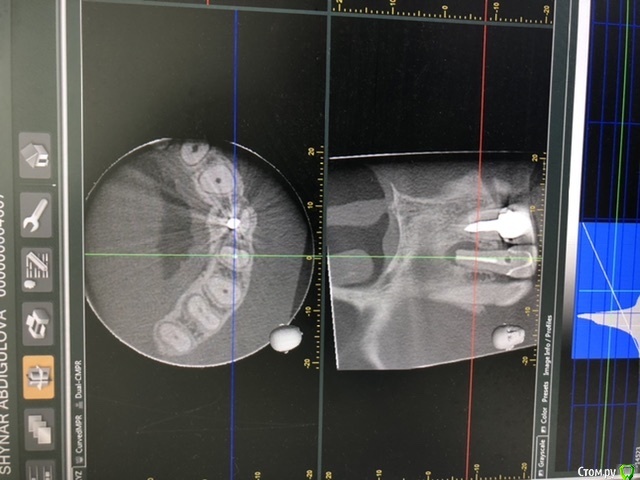

Лора777 Опубликовано 13 ноября, 2020 Автор Поделиться Опубликовано 13 ноября, 2020 Здравствуйте!Клкт посмотрите пожалуйста Ссылка на комментарий

Лора777 Опубликовано 13 ноября, 2020 Автор Поделиться Опубликовано 13 ноября, 2020 Клкт Ссылка на комментарий

Nazim_NV86 Опубликовано 13 ноября, 2020 Поделиться Опубликовано 13 ноября, 2020 До полости носа и синуса далеко. Изменения небольшие. Не вижу состояния синуса. покажите КЛКТ лору. Не можем ответить на вопрос об аллергии, т.к. нет данных про то, ложили что-то туда или нет( а если узнаем, то проверять наличие аллергии у аллерголога). Если этот зуб и виновен в рините, то только рефлекторно. Проверить это можно только его удалением (к сожалению). Ссылка на комментарий